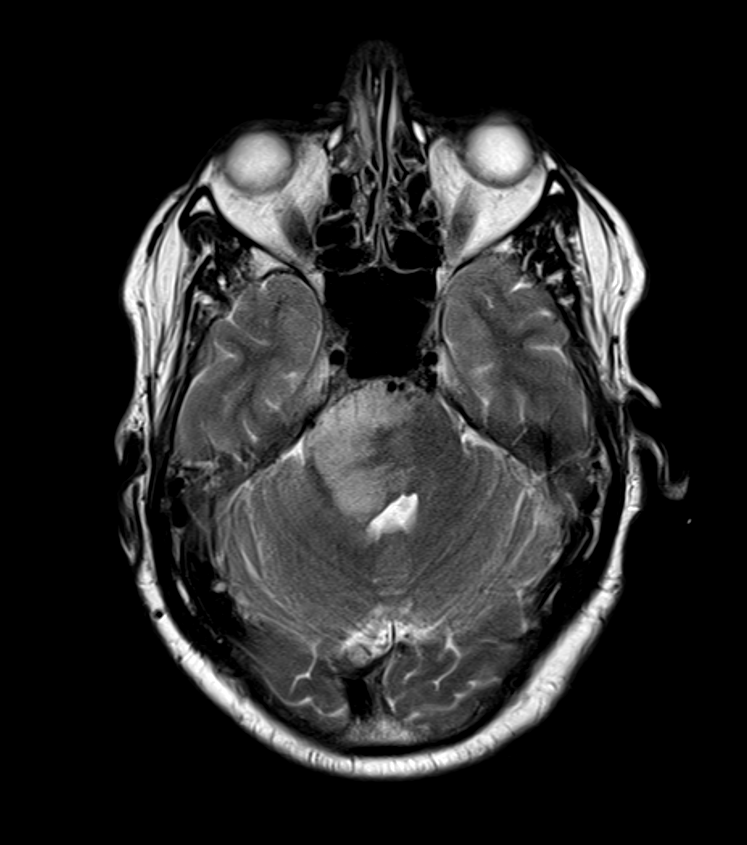

- MRI is the imaging modality of choice

- T2-weighted and FLAIR imaging:

- Hyperintense mass with infiltrative appearance

- Surrounding oedema and mass effect

- A 55-year-old patient presented with headache, nausea and vomitting.

- MRI showed an enhancing lesion in the right side of the pons with slightly reduced ADC values.

- Given an extensive travel history the imaging differential included both neoplasta and infection/inflammation.

- Biopsy revealed an H3 K27M-mutant diffuse midline glioma.